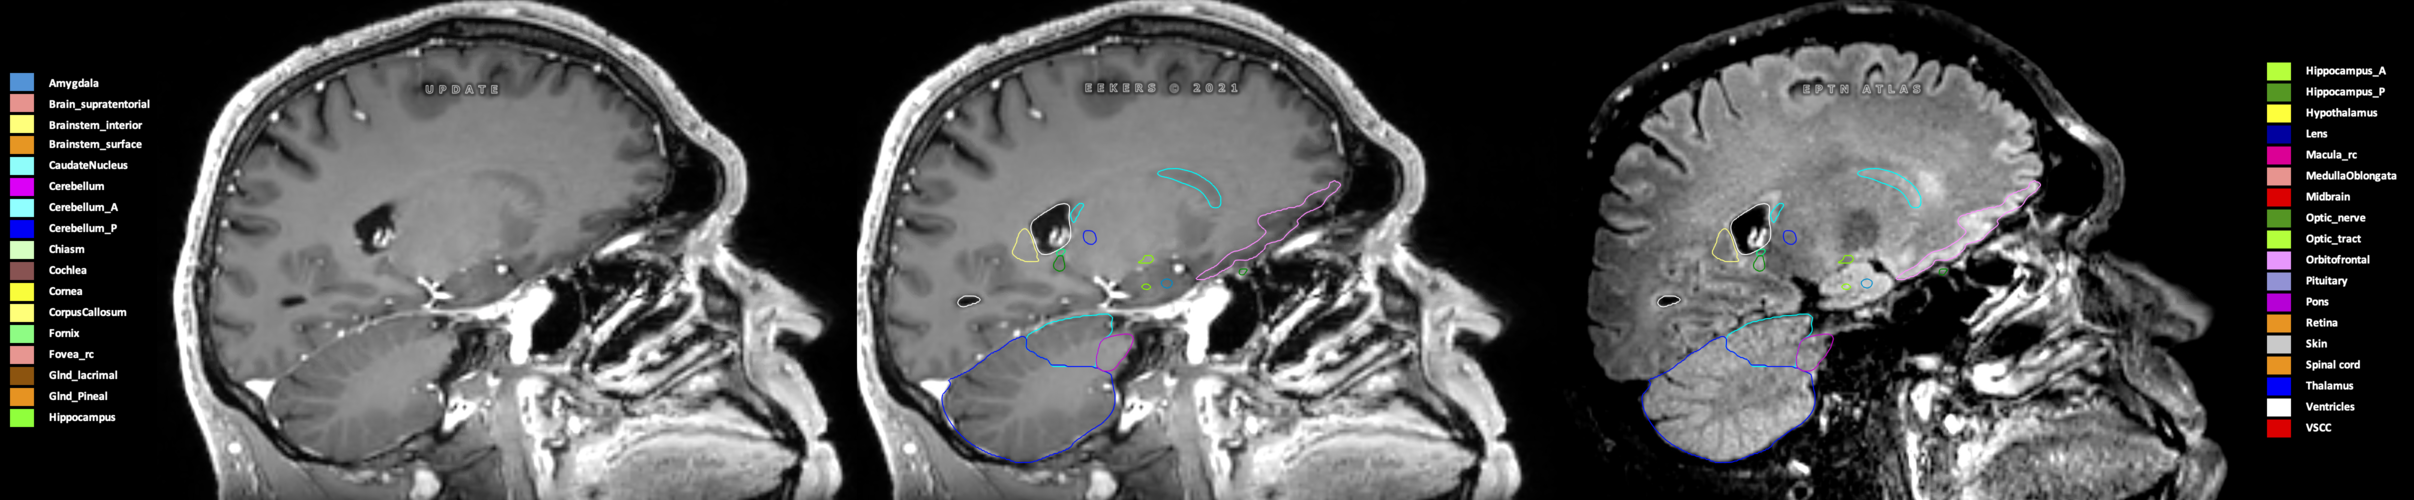

Eekers et al. have published an international neurological atlas for contouring of organs at risk in consensus with the European Particle Therapy Network (EPTN) in 2018 and an update in 2021. The purpose of this consensus atlas is to decrease inter- and intra-observer variability in delineating OARs relevant for neuro-oncology.

Included are all OARs known to be relevant for radiation-induced toxicity in neuro-oncology: brain, brainstem (midbrain, pons, medulla oblongata), chiasm, cerebellum (anterior & posterior), cochlea, cornea, hippocampus (anterior & posterior), hypothalamus, lens, lacrimal gland, optic nerve, pituitary, skin, and vestibular & semicircular canals. To further facilitate research on cognition, vision and radiological changes after irradiation of the brain, potential clinically-relevant OARs are included: amygdala, caudate nucleus, cerebellum (anterior & posterior), corpus callosum, fornix, macula, optic tract, orbitofrontal cortex, periventricular space (PVS), pineal gland, and thalamus.

Three-dimensional delineation of the 25 consensus OARs for neuro-oncology are shown on CT (WW/WL 120/40, 3000/600), 3T MR images, (T1Gd, T2FLAIR 1mm) and 7T MR (MP2RAGE 0.7 mm). All are presented in transversal, sagittal and coronal view.